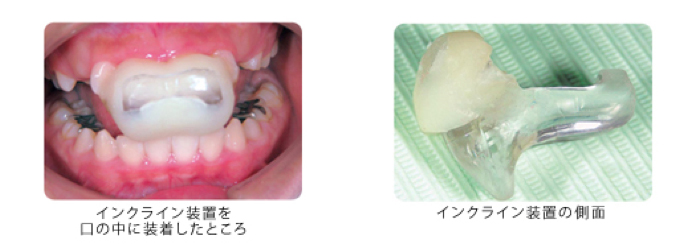

上顎前突の症例に用いる装置で、小学校3年生ぐらいから中学生頃までの患者でよく使用しています。患者自身によって取りはずしを行う簡単な矯正装置で寝る前2時間程度と寝ている間に装着します。この装置は使用しているのが家にいる時だけなので他の人に矯正治療をしていることが知られません。この装置を口の中に装着したところ、また装置を側面から見たところを写真で示します。

写真で見ると治療は大変そうに見えますが、子供達はすぐに慣れて使用できます。